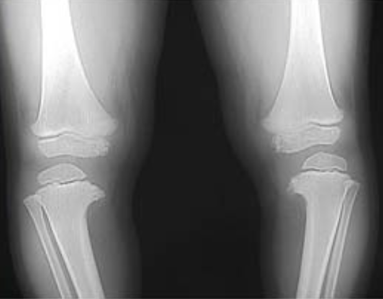

défaut de croissance du tibia interne supérieur: bilatérale 60%

- Lesion métaphysaire tibiale interne

-Angle entre physe et la diaphyse